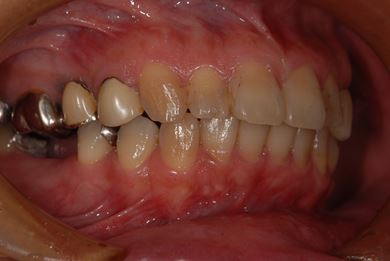

インプラントの症例写真 IMPLANT

骨再生インプラント治療

| 性別/年齢 | 女性 / 46歳 | ||||||||||||||||||||||||||||||||

| 主訴 | 歯ぐきがただれてる。歯が少しうずく。 | ||||||||||||||||||||||||||||||||

| 治療方針 | インプラント治療にて、機能的・審美的回復を行う。 | ||||||||||||||||||||||||||||||||

| 治療内容 | インプラント1本(GBR)、ハイブリッドセラミック1本 | ||||||||||||||||||||||||||||||||

| 総治療費 | 368,655円 | ||||||||||||||||||||||||||||||||

| 治療期間 | 7ヶ月 |